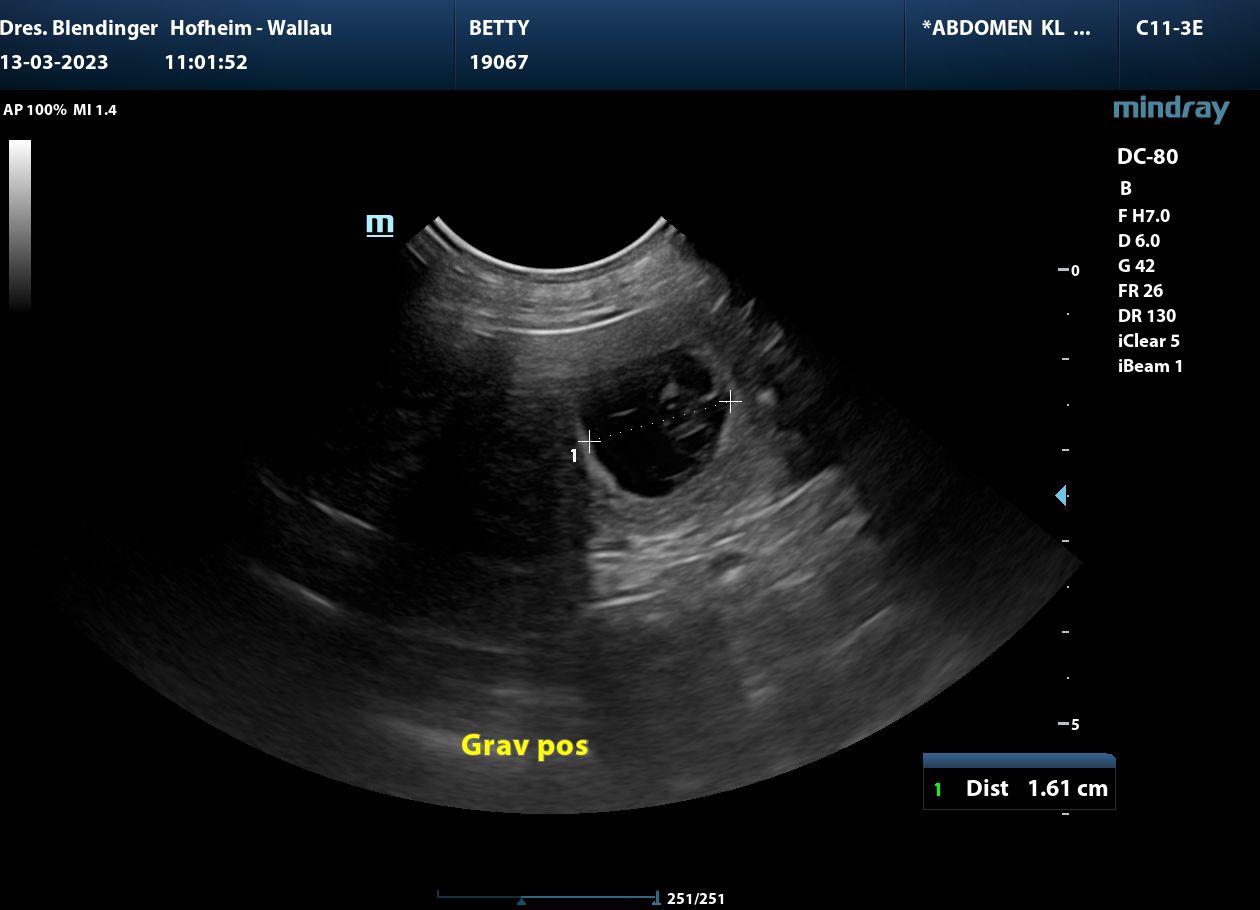

Unsere zauberhafte Betty

und

der Goldschatz Ludwig hatten ein Rendevous.

Wenn die Natur es will, werden Mitte April kleine Glücksbärchen geboren.